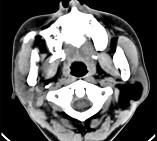

问题 男性38岁,左侧腮腺渐进性肿大1年,无压痛,CT扫描如图所示,请选择正确的描述和结论()

选项 A.左侧腮腺区见低密度肿块,CT值约为-200HU B.肿块边缘清楚,未见邻近结构受侵 C.考虑为囊肿 D.考虑为脂肪瘤 E.考虑为血管瘤

答案 ABD